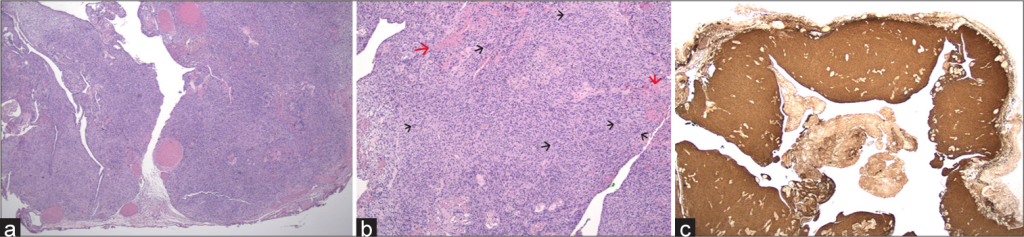

A intervenção permitiu a remoção completa do tumor. O material cirúrgico foi enviado para estudo anatomopatológico, que confirmou o diagnóstico de schwannoma plexiforme, uma lesão benigna rara da bainha dos nervos.

Imagem 2: Aspeto macroscópico da lesão após remoção cirúrgica completa.